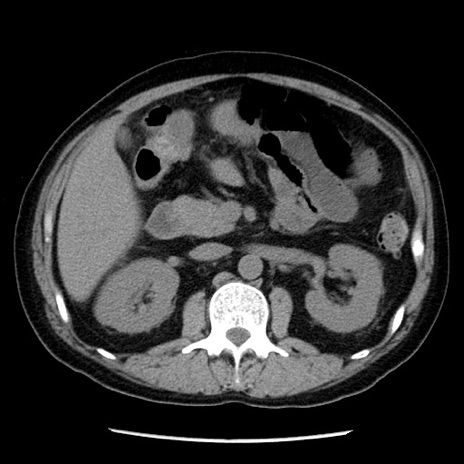

冠状断像

【症例】40歳代男性

【現病歴】2日前から胃痛あり。徐々に周期的な激痛に変化した。本日になっても激痛があるため受診。

【身体所見】意識清明、BT 38-39℃台あり、腹部:膨満、やや硬、右下腹部に圧痛あり。

【データ】WBC 8500、CRP 23.26